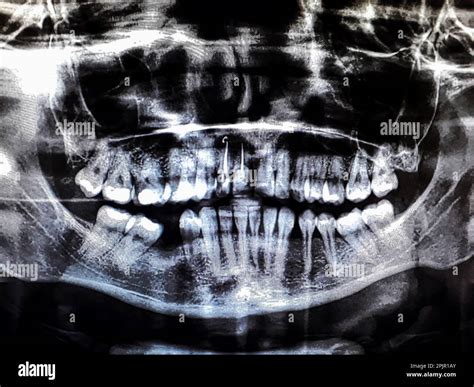

When you step into a dental office for a comprehensive examination, your dentist often suggests advanced imaging to get a complete picture of your oral health. One of the most common and vital tools in modern dentistry is the Panoramic Dental X Ray. Unlike standard bitewing or periapical X-rays that focus on one or two teeth, this imaging technique captures the entire mouth in a single, sweeping image. This includes the upper and lower jaws, all the teeth, the temporomandibular joints (TMJ), and even the surrounding sinus structures, providing a holistic view that is indispensable for accurate diagnosis and treatment planning.

The Panoramic Dental X Ray utilizes a specialized machine called an orthopantomogram (OPG). During the procedure, the X-ray tube and the digital sensor rotate in a semicircular motion around your head, capturing a continuous image of your dental anatomy. Because the human jaw is curved, the machine is calibrated to track this arc, ensuring that all dental structures remain in focus throughout the rotation.

The transition from traditional film-based X-rays to digital panoramic systems has significantly improved the quality of care. Digital sensors provide a sharper, clearer image that can be enhanced, zoomed, and filtered by your dentist to detect subtle anomalies that might not be visible to the naked eye on physical film. Additionally, digital images are easily stored in your electronic dental record, allowing your care team to track changes in your dental structure over the course of several years.